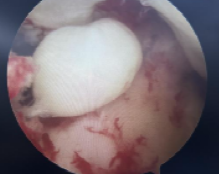

本例患者为28岁年轻女性,因意外摔伤导致左膝关节前交叉韧带完全断裂,辗转当地多家医院咨询后,最终选择前来我科手术。张智主治医师接诊患者后立即向杜恒副主任汇报,并联系尹战海主任共同讨论制定手术方案,最终确定行左膝关节镜检关节清理+半月板成形+自体腘绳肌腱重建前交叉韧带手术。

在尹战海主任的协调指导及消毒供应科的大力配合下,从总院调配关节镜设备及相关手术器械,在麻醉手术部宋珂珂、杨涵钦、李杨、高彤团队的紧密配合下,由张智主治医师主刀顺利完成手术。术后骨科任洁、孙梦媛、习姣等护理团队无缝衔接,确保了围术期无痛化管理和加速康复。术后4小时即开始无痛自主锻炼,术后1天拄拐患肢不负重活动,术后4天被动屈膝轻松达到90度,今日顺利出院继续院外康复。

2025年1月10日,我院骨科陆港院区再接再厉,单日又完成3例关节镜微创手术。分别为13岁女性外侧盘状半月板撕裂患者行半月板成形缝合修复术,为21岁男性陈旧性前交叉韧带断裂患者行自体肌腱前交叉韧带重建术,为58岁女性骨关节炎膝关节游离体患者行关节清理游离体取出术。目前这些患者均康复良好,拟于近期出院。